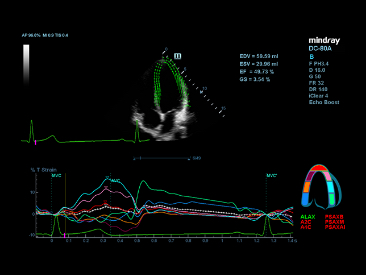

Echo Boost yang canggih

Terobosan beruntun Mindray untuk visualisasi gambar ultrasound terbaik.

eXceptional intelligence

Kecerdasan di seluruh alur kerja yang ada

Untuk meningkatkan efisiensi pemindaian dengan akurasi dan konsistensi yang lebih tinggi, X-Insight memberikan kecerdasan luar biasa di seluruh alur kerja ujian, mulai dari akuisisi pesawat hingga pengoptimalan gambar, dan dari penghitungan hingga protokol ujian.